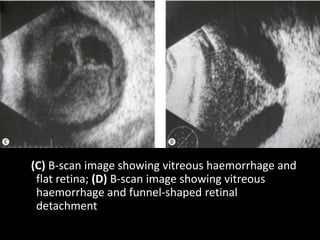

(C) B-scan image showing vitreous haemorrhage and

flat retina; (D) B-scan image showing vitreous

haemorrhage and funnel-shaped retinal

detachment